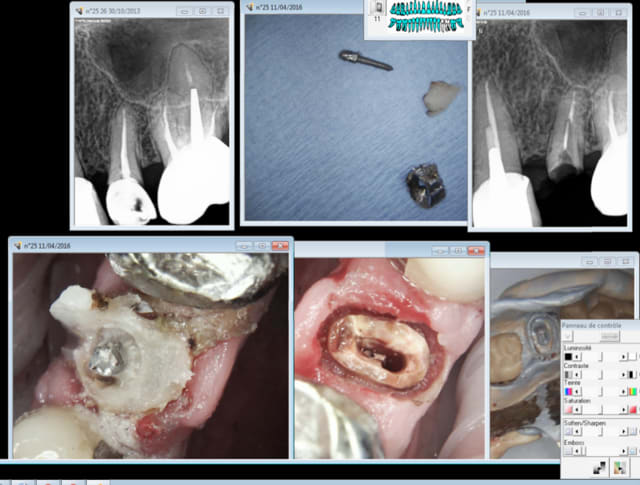

chicot29

11/04/2016 à 18h53

Numéro 1. -)

Capture d e cran 2016 04 11 16.52 - Eugenol

Dsc05680 medium aphmfg - Eugenol

Sais pas. Mais la résine auto j'ai eu un peu plus tot dans la journée. Un trois quart de couronne avec une technique sandwich compo en vestibulaire et résine auto autour du screw post. -)

Cas N° 2. -)

Capture d e cran 2016 04 12 00.47 - Eugenol